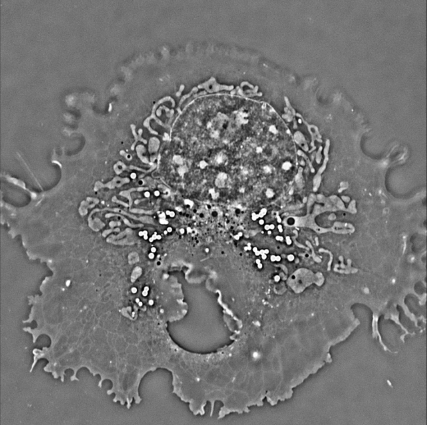

“原位高时空分辨双模式显微成像仪”是一款完全自主研发、具备技术颠覆性与全球竞争力的高端科学仪器。该产品基于光穿过样品时引发的相位变化,能够定量获取透明活细胞内细胞器的三维形貌与折射率分布,具有200纳米的全向空间分辨率、250帧/秒的时间分辨率以及纳米级的检测灵敏度。产品创新性地提出“单相机双模式”融合设计,成功攻克了传统活细胞成像中“光毒性强、难以长期观测”的世界性难题,以亚像素级匹配精度实现了荧光与定量相位的原位双模式成像。结合人工智能数字染色技术,无需荧光标记即可自动识别并对细胞器进行数字染色,可对活细胞内细胞器进行长达数天的无损、高分辨连续观测。

该产品突破了高原细胞实验的时空限制,能够对高原低氧及紫外刺激等特殊环境下的活细胞进行原位高分辨检测。配套自主研发的微流控芯片,可精准调控细胞生存的微环境并实施药物刺激,为高原医学研究及中药现代化开发提供了前所未有的工具,高度契合青海省产业发展战略。在性能全面超越同类进口设备的同时,成本大幅降低,有效打破了国外技术垄断,展现出广阔的国产替代潜力和市场应用前景。该项目核心技术由9项已授权发明专利、4项已提交发明专利及4项相关奖项提供支撑,经科学技术成果评价认定为国内领先水平,具备完全独立自主知识产权。